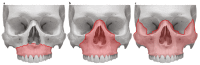

Fractures of the midface pose a serious medical problem as for their complexity, frequency and their socio-economic impact. Interdisciplinary approaches and up-to-date diagnostic and surgical techniques provide favorable results in the majority of cases though. Traffic accidents are the leading cause and male adults in their thirties are affected most often. Treatment algorithms for nasal bone fractures, maxillary and zygomatic fractures are widely agreed upon whereas trauma to the frontal sinus and the orbital apex are matter of current debate. Advances in endoscopic surgery and limitations of evidence based gain of knowledge are matters that are focused on in the corresponding chapter. As for the fractures of the frontal sinus a strong tendency towards minimized approaches can be seen. Obliteration and cranialization seem to decrease in numbers. Some critical remarks in terms of high dose methylprednisolone therapy for traumatic optic nerve injury seem to be appropriate. Intraoperative cone beam radiographs and preshaped titanium mesh implants for orbital reconstruction are new techniques and essential aspects in midface traumatology. Fractures of the anterior skull base with cerebrospinal fluid leaks show very promising results in endonasal endoscopic repair.